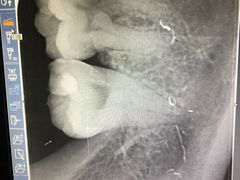

• 瑞尔齿科(南京东路名人诊所)

• -瑞尔齿科(南京东路名人诊所)

1122mummy | 19-04-15